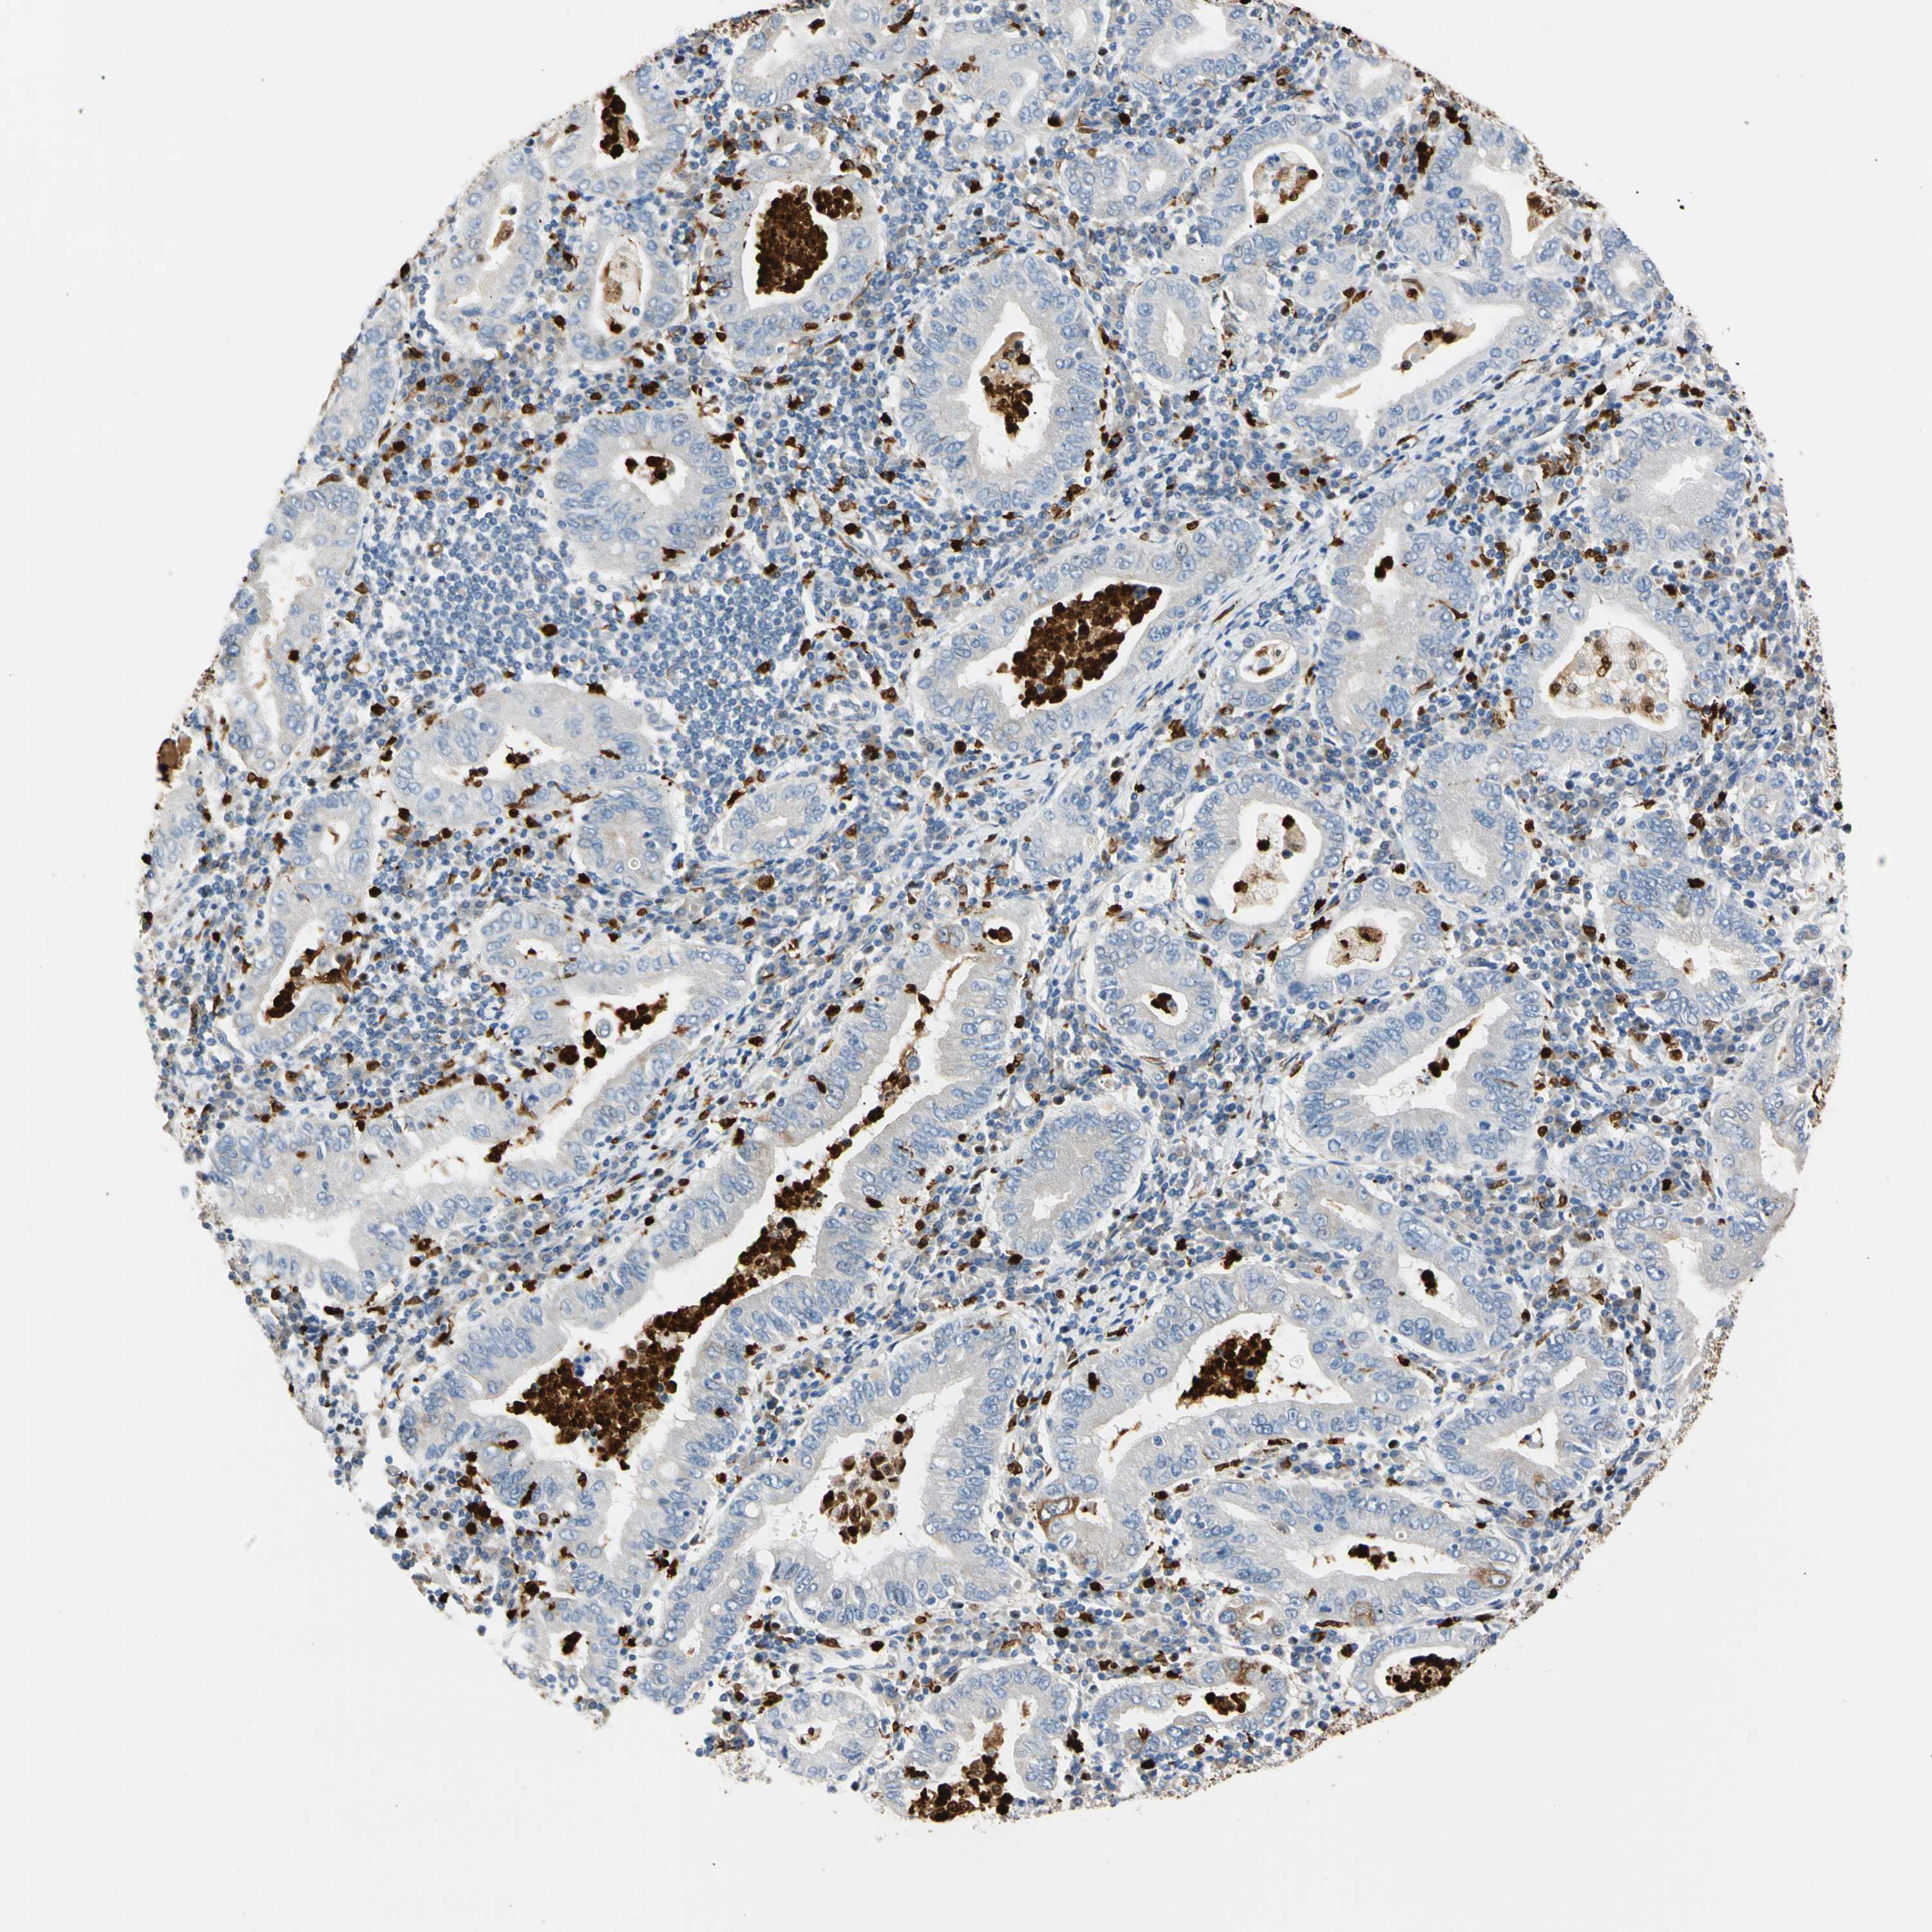

STOMACH CANCER - Protein expressioni

A mouse-over function shows sample information and annotation data. Click on an image to view it in a full screen mode. Samples can be filtered based on level of antibody staining by selecting one or several of the following categories: high, medium, low and not detected. The assay and annotation is described here.

Note that samples used for immunohistochemistry by the Human Protein Atlas do not correspond to samples in the TCGA dataset.

Antibody stainingi

Antibody staining in the annotated cell types in the current human tissue is reported as not detected, low, medium, or high, based on conventional immunohistochemistry profiling in selected tissues. This score is based on the combination of the staining intensity and fraction of stained cells.

Each image is clickable and will lead to virtual microscopy that enables deeper exploration of all samples and also displays staining intensity scores, fraction scores and subcellular localization as well as patient and tissue information for each sample.

Antibody HPA008052

Antibody CAB010277

Staining

High

Medium

Low

Not detected

Intensity

Strong

Moderate

Weak

Negative

Quantity

>75%

75%-25%

<25%

None

Location

Nuclear

Cytoplasmic/membranous

Cytoplasmic/membranous,nuclear

Adenocarcinoma, NOS

Adenocarcinoma, High grade